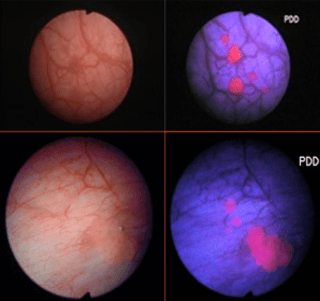

NARROW BAND IMAGE

Permite diferenciar el contraste entre el urotelio normal y el tejido tumoral hipervascular. Parece demostrarse una mejora en la detección del cáncer mediante biopsia y RTU V guiada por Narrow Band Image (NBI). Aún no se ha demostrado que el uso de esta medida disminuya la tasa de recurrencia tras RTU V.

DIAGNOSTICO FOTODINAMICO PDD

Utiliza la luz azul en combinación con un fotosensibilizador – Acido 5 Aminolaevulinico (5-ALA) o Acdio Hexaminolaevulinico (HAL) – bsado en estudios que demostraron que existían tumores que no podían detectarse mediante luz blanca convencional.

Utiliza la luz azul en combinación con un fotosensibilizador – Acido 5 Aminolaevulinico (5-ALA) o Acdio Hexaminolaevulinico (HAL) – bsado en estudios que demostraron que existían tumores que no podían detectarse mediante luz blanca convencional.

El PDD tiene una mayor sensibilidad (92 % vs 71 %) para la detección del CIS que la luz blanca; aunque la especificidad es francamente inferior (63 %Ç vs 81 % )

MU POINT sobre el PDD

Un Estudio Prospectivo Randomizado NO CONFIRMO mayores tasas de detección en pacientes con Citología de orina positiva conocida previamente.

Los estudios Prospectivos Randomizados son controversiales al intentar demostrar una disminución en las tasas de recurrencia con el uso de RTU V utilizando ALA.

Tiene Falsos Positivos en relación a la inflamación post RTU V y por BCG incluso tras 3 meses de la terapia.

Un Metaanalisis demostró disminución del 10 % en las tasas de recurrencia ea los 12 meses en todos los grupos.

Permanece por aclarar si disminuye las tasas de progresión y de supervivencia.